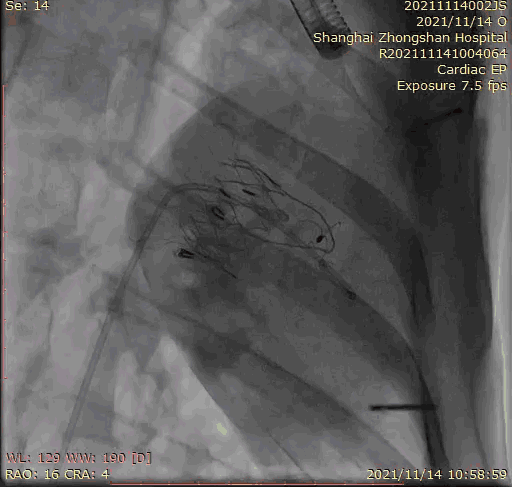

上海中山醫(yī)院葛均波院士、錢菊英院長(zhǎng)、周達(dá)新教授、潘文志教授、潘翠珍教授、李偉教授共同完成此次臨床前研究。術(shù)后葛均波院士對(duì)Lux-Valve Plus的器械操作性能給予了高度評(píng)價(jià),DSA和超聲影像也顯示出在本次研究中Lux-Valve Plus的安全性和有效性俱佳。

本次臨床前研究經(jīng)右側(cè)頸靜脈置入LuX-Valve Plus輸送系統(tǒng)可調(diào)彎鞘管,在DSA及超聲引導(dǎo)下將人工三尖瓣瓣膜植入到原有三尖瓣位置,利用獨(dú)特的錨定技術(shù)將人工瓣膜支架可靠固定在預(yù)定的位置。